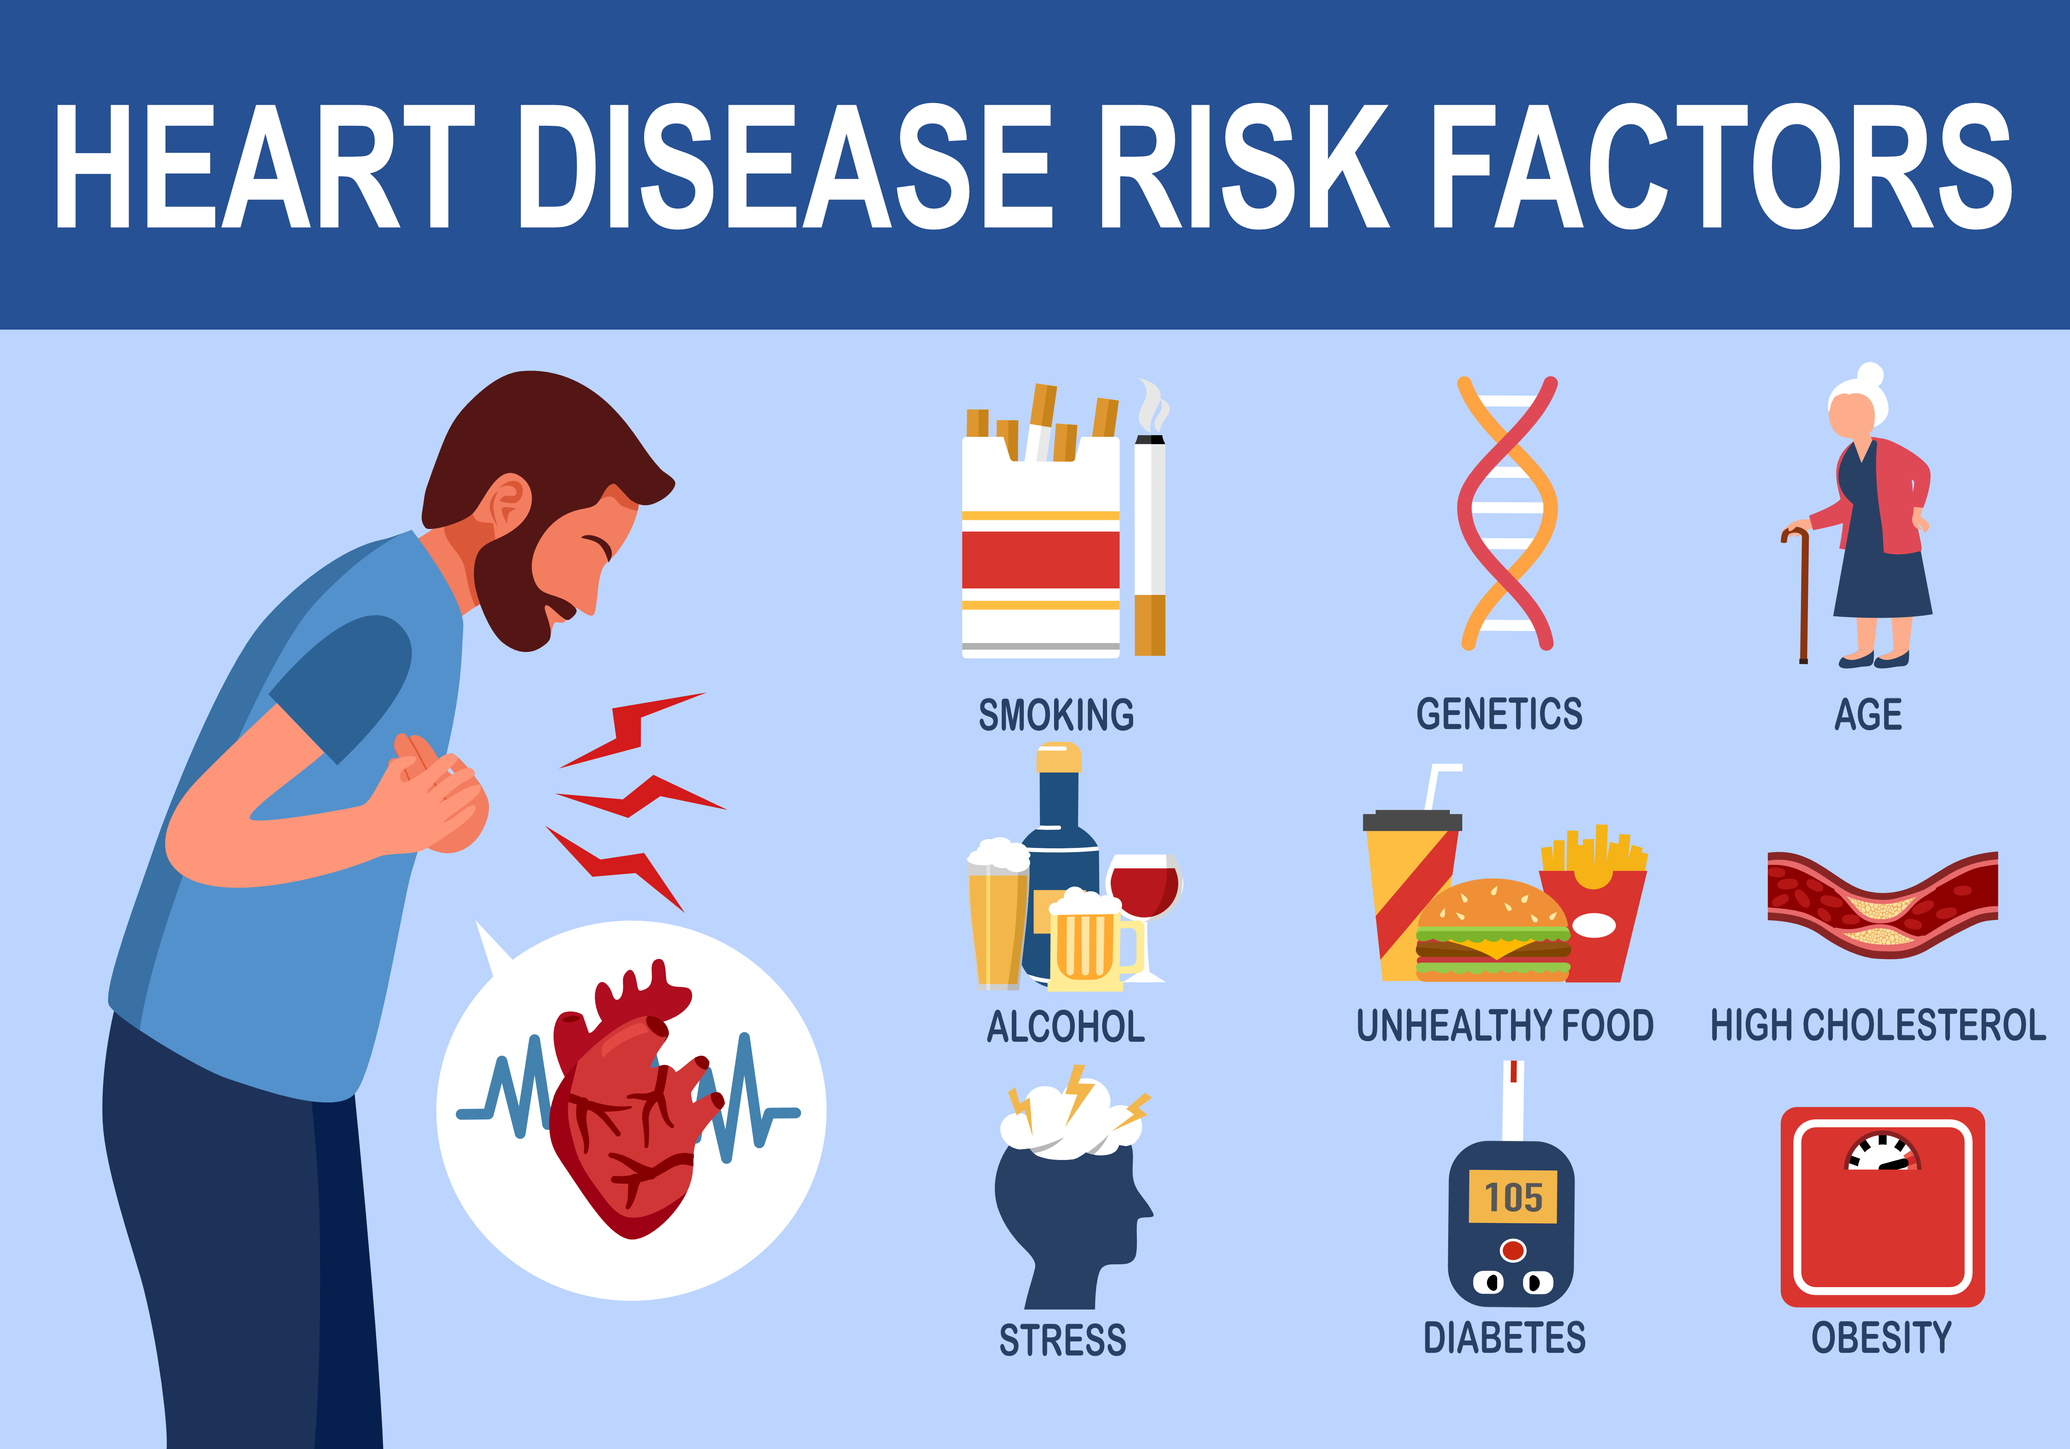

Why Is Heart Health Important To Talk About In The Workplace

Why Is Heart Health Important To Talk About In The Workplace